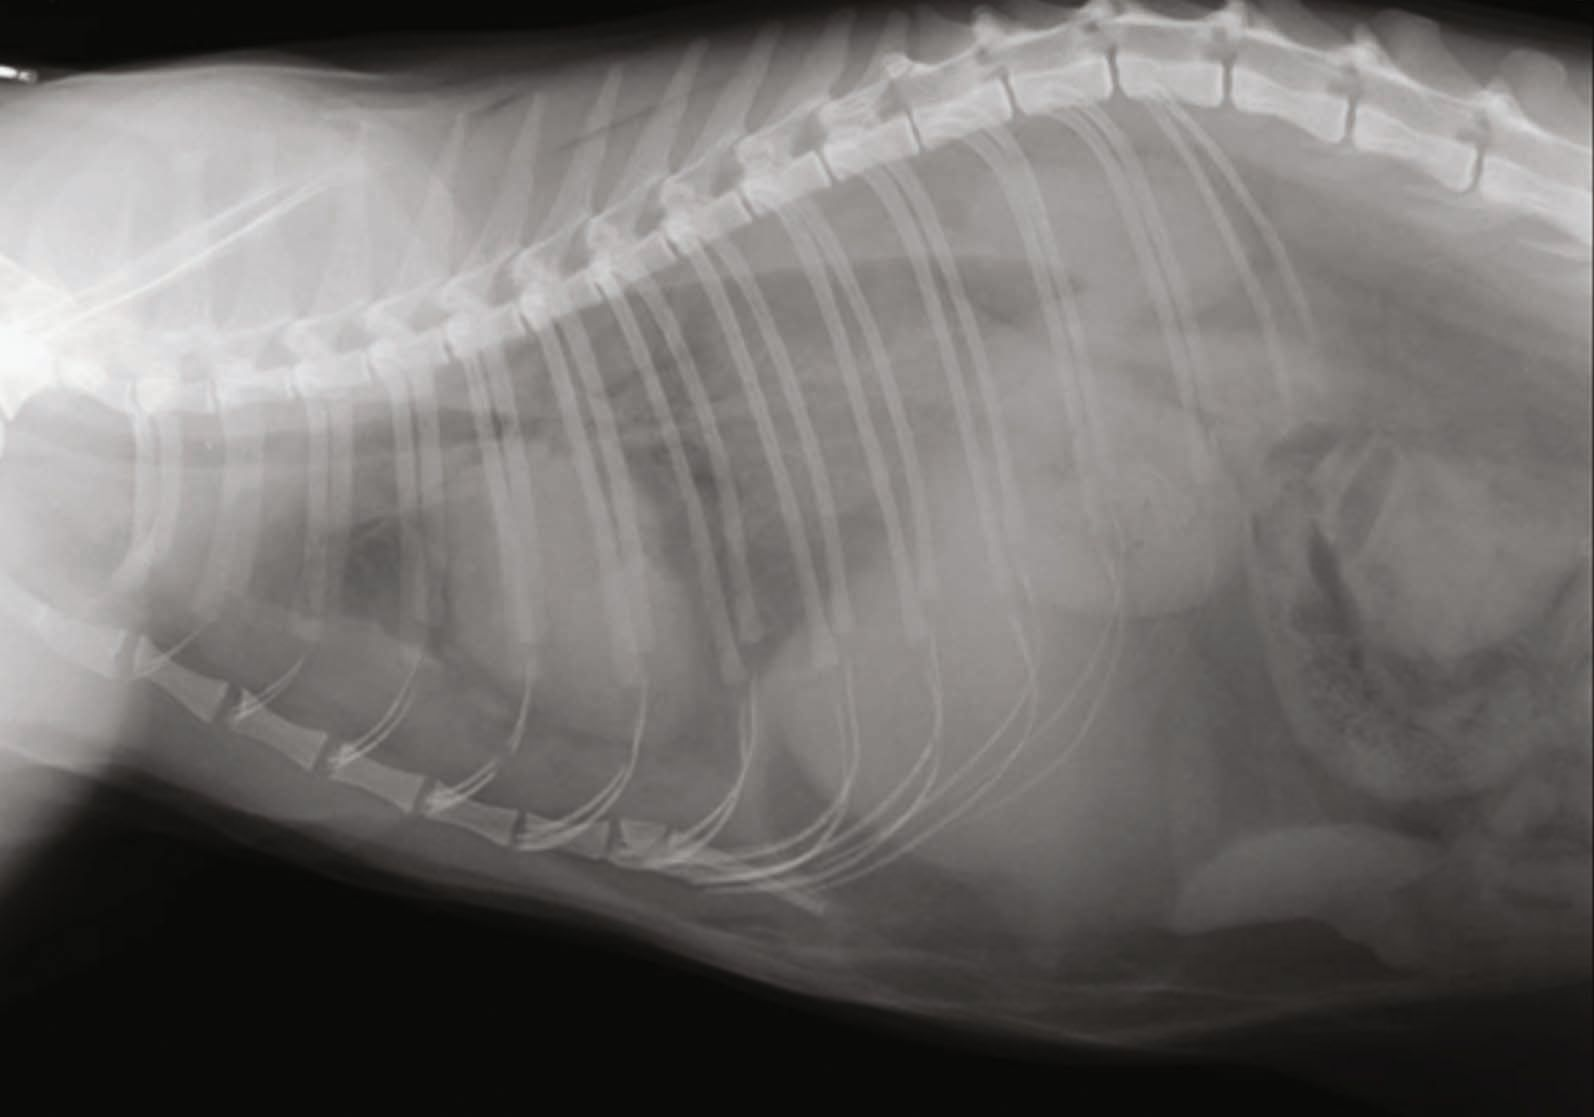

Right lateral radiographs of 4 dogs with caval foramen liver hernias Where Is A Dogs Hernia They’re often diagnosed in young puppies. Hernias in dogs are common conditions where internal body parts push through weakened muscles or body walls. Symptoms of a hernia in a dog include fever, lethargy and even vomiting;. Yes, dogs can get hernias. A hernia can obstruct some of your dog's bodily functions, resulting in gastrointestinal, digestive, or breathing problems depending on. Where Is A Dogs Hernia.

Dog X Ray. Diaphragmatic Hernia in Dog. Stomach Herniated in the Thorax Where Is A Dogs Hernia A hernia occurs when a tear in a muscle wall or fatty tissue allows the contents of a dog’s stomach to push through that opening. Yes, dogs can get hernias. Read our guide to hernia in dogs, and you’ll discover: A hernia can obstruct some of your dog's bodily functions, resulting in gastrointestinal, digestive, or breathing problems depending on the. Where Is A Dogs Hernia.